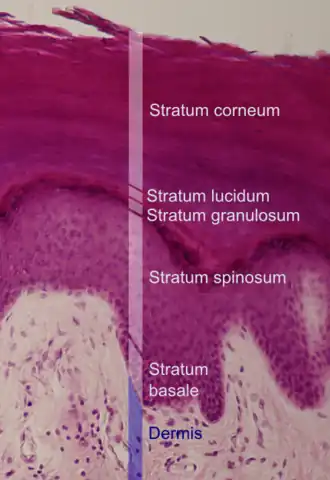

Histologic image of human epidermis in thick skin | |

The stratum corneum (Latin for 'horny layer') is the outermost layer of the epidermis of the skin. Consisting of dead tissue, it protects underlying tissue from infection, dehydration, chemicals, and mechanical stress. It is composed of 15 to 20 layers of flattened cells with no nuclei or cell organelles.

Structure

The human stratum corneum comprises several levels of flattened corneocytes that are divided into two layers: the stratum disjunctum and stratum compactum. The stratum disjunctum is the uppermost and loosest layer of skin. The skin's protective acid mantle and lipid barrier sit on top of the stratum disjunctum.[5] The stratum compactum is the comparatively deeper, more compacted and more cohesive part of the stratum corneum.[6] The corneocytes of the stratum disjunctum are larger, more rigid and more hydrophobic than those of the stratum compactum.[7]

The thickness of the stratum corneum varies throughout the body. In the palms of the hands and the soles of the feet (sometimes knees, elbows,[9] and knuckles) this layer is stabilized and built by the stratum lucidum (clear phase) which allows the cells to concentrate keratin and toughen them before they rise into a typically thicker, more cohesive stratum corneum. The mechanical stress of heavy structural strain causes this stratum lucidum phase in these regions which require additional protection in order to grasp objects, resist abrasion or impact, and avoid injury. In general, the stratum corneum contains 15 to 20 layers of corneocytes. The stratum corneum has a thickness of between 10 and 40 μm.